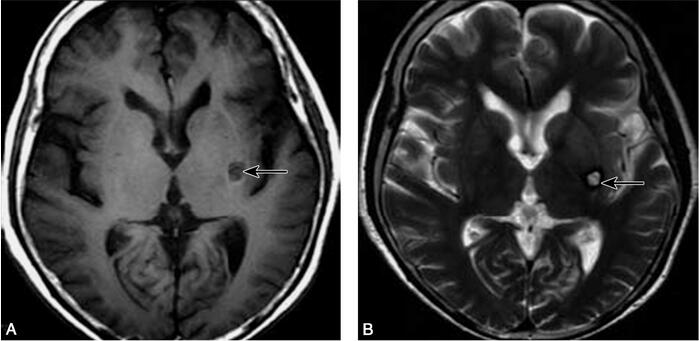

1小时条评论1 病例简介 患者女,83岁,因右侧肢体不自主运动20余天于2007年1月10日来我院急诊就诊。患者入院前20余天无明显诱因出现右手不自主抖动,症状逐渐加重,出现右侧肢体不自主运动,为快速、无目的、无节律、粗大舞蹈样动作,伴右侧噘嘴、舌部不自主活动,意志不能控制...